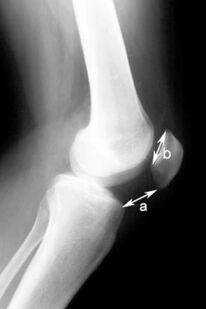

Особенно велико значение бокового снимка для изучения бедренно-надколенникового сочленения. В оценке топографии надколенника применяются различные коэффициенты измерения, из которых наиболее используемый - индекс Катона). Для измерения этого индекса требуется снимок, произведенный при сгибании коленного сустава на 30°.

Индекс Катона является соотношением расстояния от нижнего края надколенника до передне-верхнего угла большеберцовой кости к длине суставной поверхности надколенника (рис. 3). В норме это соотношение обычно равно 1± 0,3.

Рисунок 3. Индекс Катона. Объяснения в тексте.

Слишком высокое расположение надколенника (patella alta) приводит к запоздалому его внедрению в трохлеарное устье, что может являться причиной бедренно-надколенниковой нестабильности.